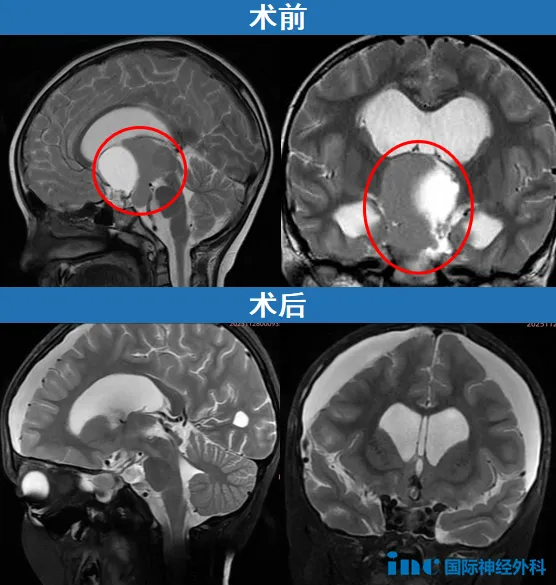

经过焦灼的等待,田先生一家迎来了好消息。小安的肿瘤实现肉眼全切,垂体柄得以完整保留。近期随访时,巴教授的诊断意见更让家人安心:"影像学显示肿瘤切除效果极佳,未出现任何负面并发症。考虑到手术仅过去四周,且是一次高难度复杂手术,患儿目前的恢复状况令人欣慰。"

2024年12月,小安首次出现头痛症状,初诊被怀疑为鼻窦炎。直至今年上半年头痛复发,伴有不愿上学等表现,家人始觉异常。期间虽经历搬家环境变化,但间歇性头痛始终未引起重视。直至出现喷射性呕吐、头痛加剧、行走不稳等典型症状后,MRI检查才揭示鞍上延伸至第三脑室和桥小脑角区的巨大颅咽管瘤,并已继发脑积水。

经过一周准备,小安于11月12日接受手术。手术室外的祝福对联、小熊挂件和卡通玩偶共同为患儿加油。手术取得圆满成功,不仅实现肿瘤肉眼全切,垂体柄也获得保留。术后患儿未需进入ICU监护,直接返回普通病房。

由于术前近6cm肿瘤对视神经造成压迫,加之脑积水影响,患儿存在视野受限问题。但巴教授认为这属于可逆性损伤,经过数月休养有望逐渐恢复。家人用"抓虫子"的比喻鼓励小安,术后其四肢活动、神经功能、记忆思维等均保持良好状态。